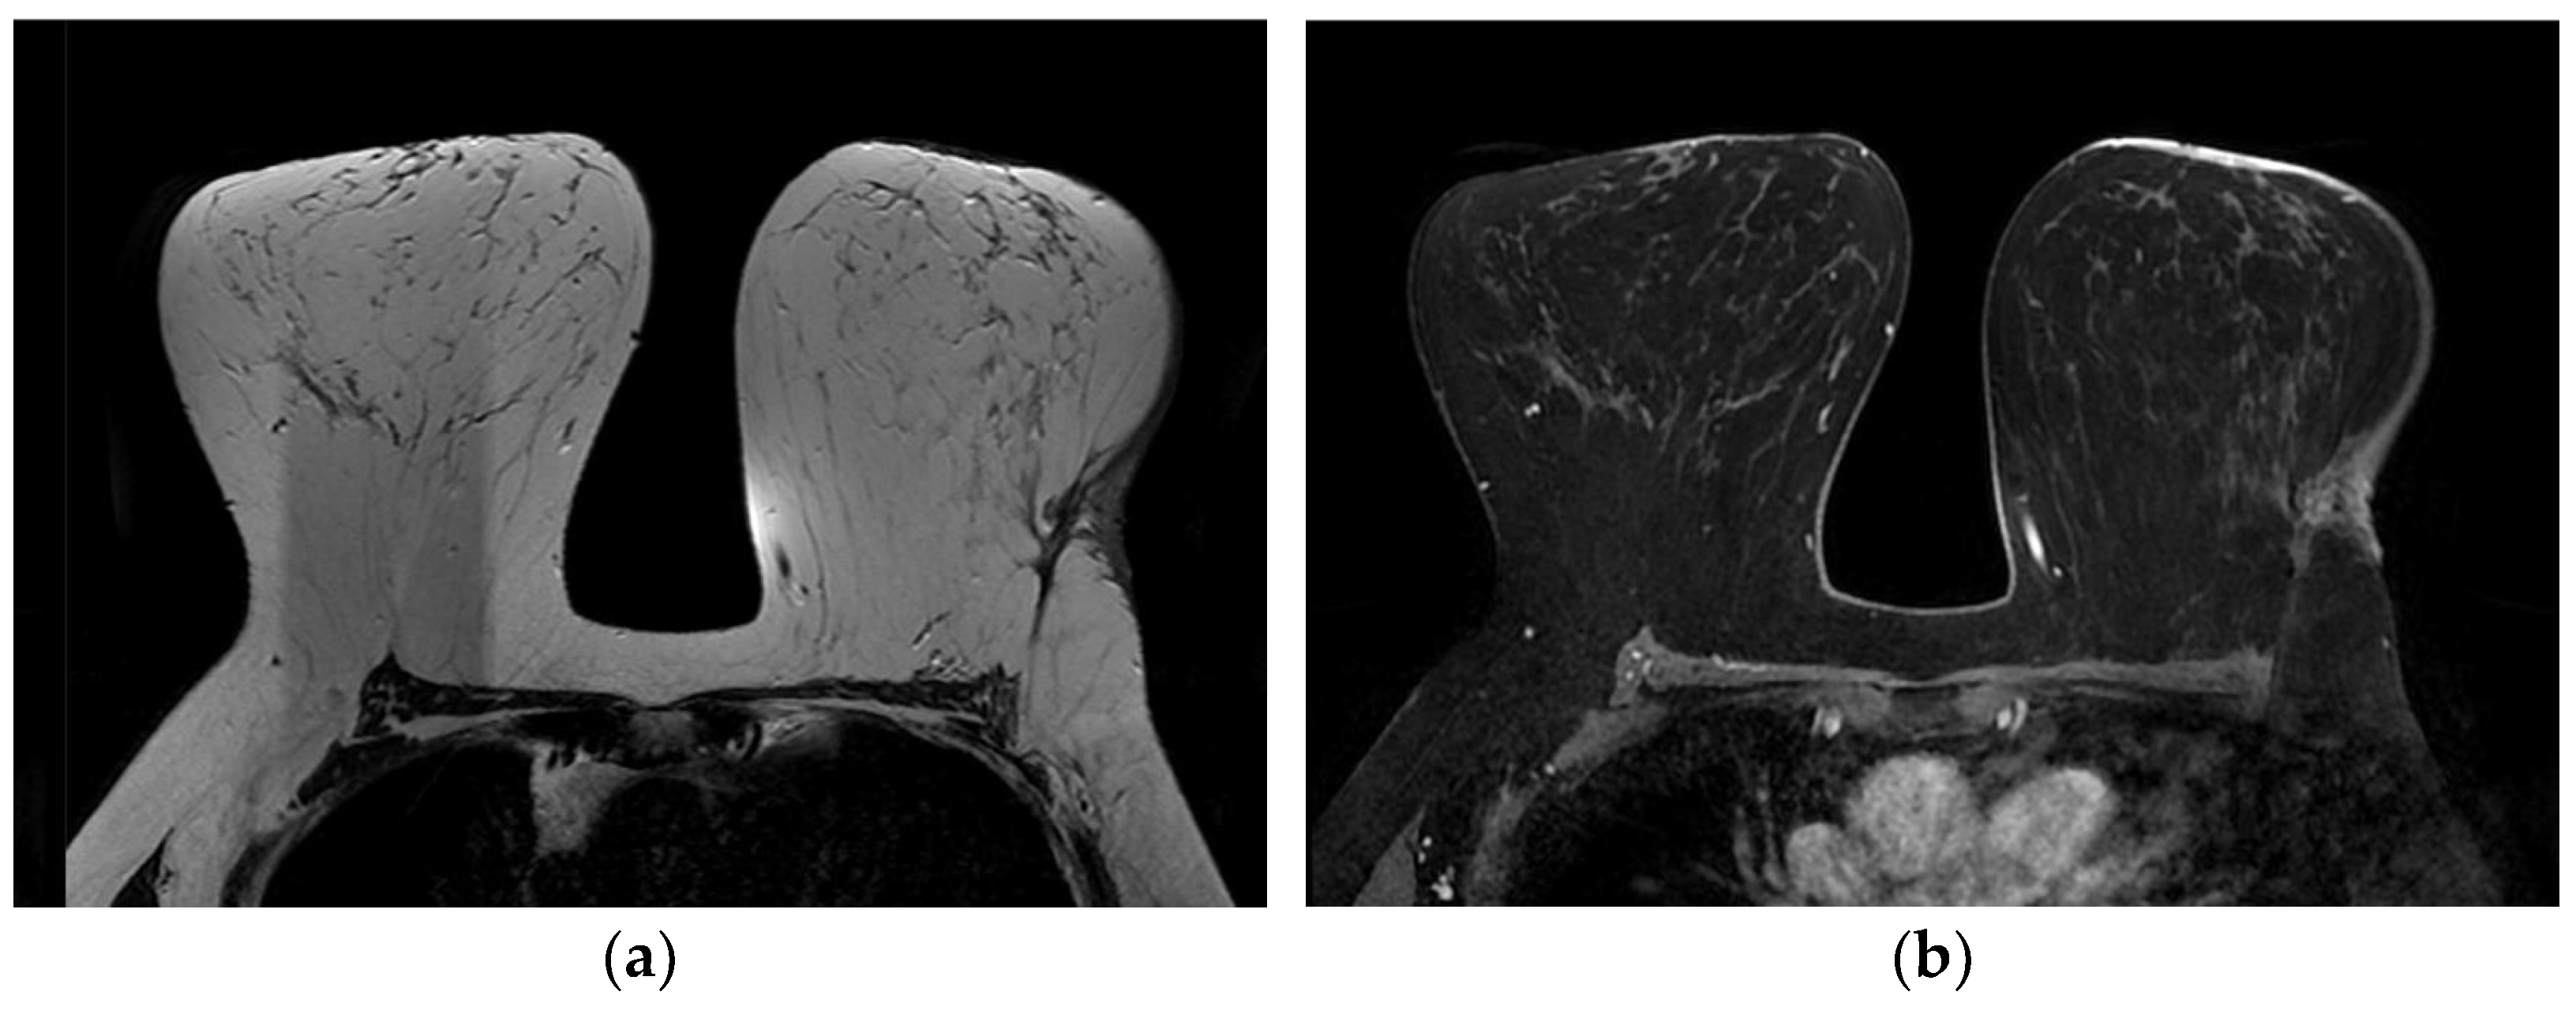

4.3. Magnetic Resonance Imaging